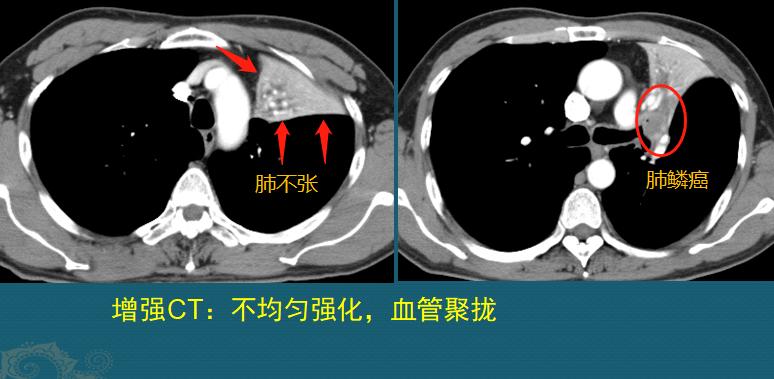

上图这位男子51岁,抽烟30年,因为咳嗽、痰中带血发现右侧中心型肺癌,支气管镜取病理确诊为肺鳞癌,距离气管隆突太近了,后来经过放疗为主的综合治疗,肿瘤萎缩消散,至今4年多了没有复发:

上图是一位52岁男子,多年吸烟,查出左侧中心型肺鳞癌(右图光圈内),肿瘤阻塞左肺上叶支气管,造成远侧肺组织气体吸收,发生阻塞性肺不张。